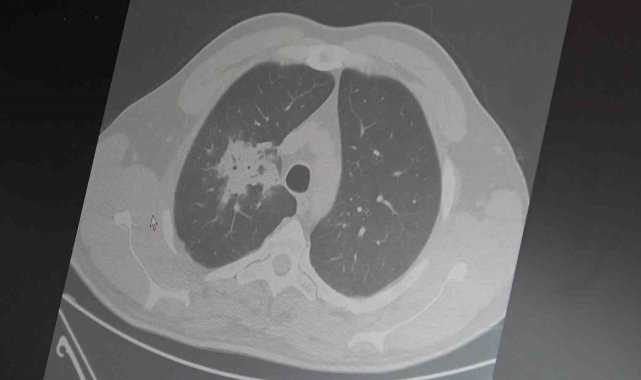

Göğüs Hastalıkları Uzmanı Prof. Dr. Şevket Özkaya, elektronik sigaralara ilişkin yapılan bilimsel çalışmaların sonuçlarının netleşmeye başladığını belirterek, "100'den fazla çalışma analiz edildi ve sonuç açıktır; elektronik sigara kansere neden olur" dedi.Elektronik sigaraların 2000'li yılların başında geleneksel sigaraya göre daha temiz, daha az kokulu ve daha güvenli bir alternatif olarak pazarlandığını hatırlatan Prof. Dr. Özkaya, milyonlarca kişi tarafından hızla benimsendiğini söyledi. Kullanıcıların yıllardır "Zararı var mı, sigaraya göre daha mı zararsız" sorusunu yönelttiğini ifade eden Özkaya, "Biz her zaman bu tür ürünlerin zararlarının en az 20-30 yıllık kullanım sonrası ortaya çıkacağını söyledik. Bu süre doldu ve bilimsel veriler gelmeye başladı" diye konuştu."Kanser riskini artırıyor"100'den fazla bilimsel çalışmanın incelendiği kapsamlı analizlere dikkat çeken Özkaya, elektronik sigaraların özellikle temas ettiği akciğer ve ağız bölgelerinde kanser riskini artırabileceğine dair güçlü bulgular bulunduğunu belirtti. Uzun vadeli sonuçların henüz tam olarak ortaya çıkmadığını ancak erken uyarı işaretlerinin ciddi olduğunu vurguladı. Araştırmalarda insan, hayvan ve laboratuvar verilerinin birlikte değerlendirildiğini aktaran Özkaya, elektronik sigaraların içerdiği kimyasalların hücre düzeyinde zarara yol açtığının ortaya konulduğunu ifade etti.Hücre düzeyinde ciddi hasarElektronik sigaraların DNA hasarı, oksidatif stres ve kronik iltihaplanma gibi kanser gelişiminde kritik rol oynayan üç temel mekanizmayı tetiklediğini belirten Özkaya, "Bu üç faktörün doğrudan kanser oluşumuna neden olduğunu biliyoruz" şeklinde konuştu."Çifte kullanım riski 4 kat artırıyor"2024 yılında yayımlanan bir çalışmaya da değinen Özkaya, hem geleneksel sigara hem de elektronik sigara kullanan bireylerde akciğer kanseri riskinin, sadece sigara içenlere göre dört kat daha fazla olduğunun bildirildiğini kaydetti.Gençler için uyarıElektronik sigara kullanımının özellikle gençler arasında yaygınlaştığını ifade eden Özkaya, lise çağındaki bireyler ve 40 yaş altındaki kişilerde kullanım oranlarının arttığına dikkat çekti. Elektronik sigara ile başlayan gençlerin ilerleyen süreçte normal sigaraya geçiş yapma ihtimalinin daha yüksek olduğunu belirtti. Özkaya, erken bilimsel bulguların göz ardı edilmemesi gerektiğini vurgulayarak, "Bugün gerekli önlemler alınmazsa, gelecekte çok daha büyük bir halk sağlığı sorunu ile karşı karşıya kalabiliriz" ifadelerini kullandı.